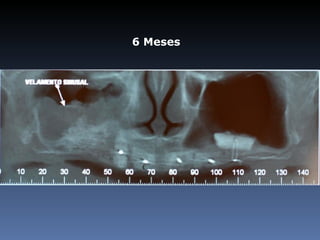

Teresinha Soares Galindo

Idade – 68 anos

Sexo – Feminino

Raça – Caucasiana

ASA – II

Data- 23-04-2012

Diagnóstico:Desdentada total maxila

Plano de tratamento:          Reabilitação com 6 blocos

“onlay” e “sinus-llift” bilateral, provenientes de Úmero

fresco-congelado (FFB); reabertura para instalação

de 6 implantes dentários endo-ósseos e reabilitação

protética fixa.

6 Meses